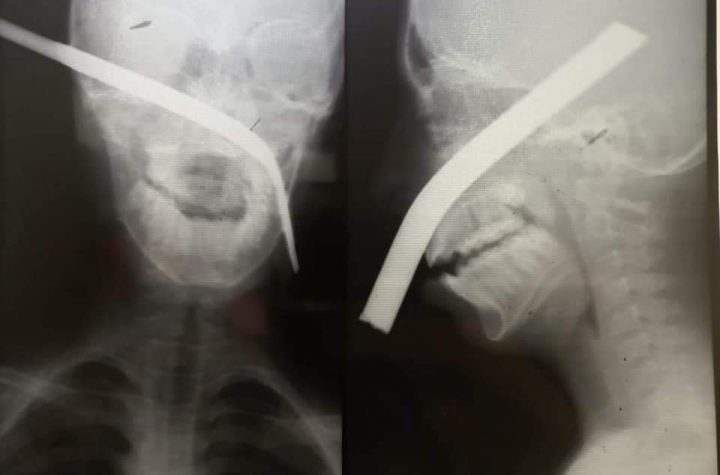

كتبت-انجى ماهر شهد مستشفى خاص في مدينة الفشن جنوب بني سويف، حالة...